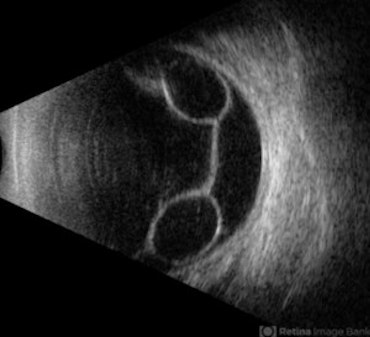

Rhegmatogenous Retinal Detachment

Color fundus photograph of left eye showing rhegmatogenous retinal detachment.